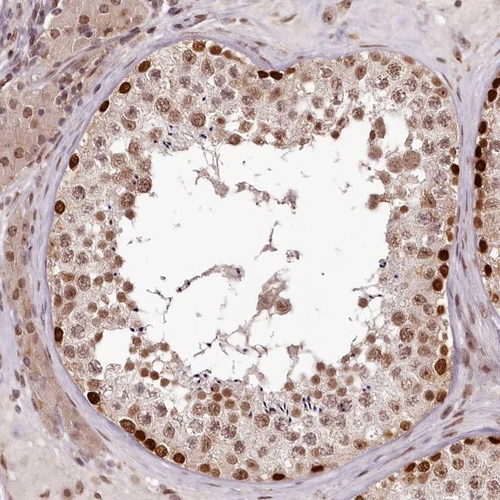

Immunohistochemical staining of human testis shows strong nuclear positivity in cells in seminiferous ducts.